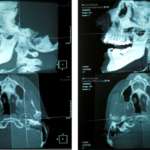

Viene proposta una metodica per diagnosticare alterazioni patologiche dell’ATM, dei mascellari, delle vertebre cervicali, mettere in relazione queste strutture anatomiche e applicare alle loro immagini i riferimenti di tracciati cefalometrici già conosciuti e/o nuove correlazioni.

Studio clinico comparativo fra una metodica cefalometrica radiation free e la cefalometria tradizionale

In ortognatodonzia si trattano spesso pazienti nel corso dell’infanzia e dell’adolescenza, durante fasi attive di crescita. Risulta quindi evidente l’importanza di evitare la loro...